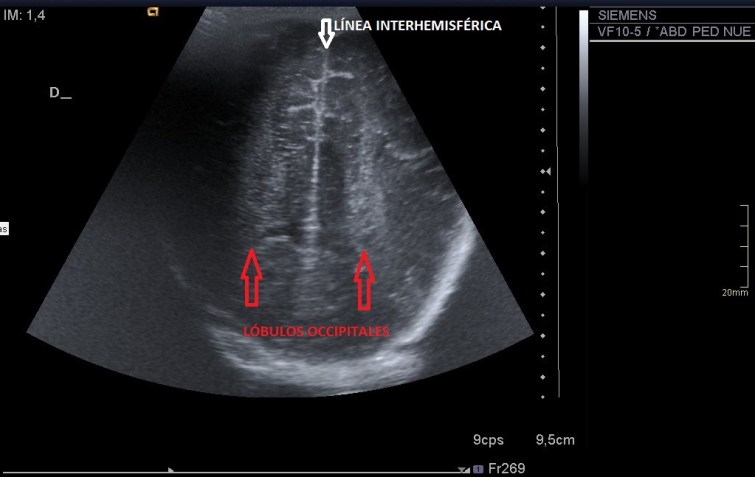

- –LÓBULO OCCIPITAL

-OCCIPITAL LOBE

Corte 6:

Has visto que en algunos cortes he puesto alguna imagen más, para que comprendas mejor y puedas buscar mejor la anatomía ecográfica y obviamente, yo lo hago, siempre saco más imágenes que los 6 estándar mínimos que hay que realizar.